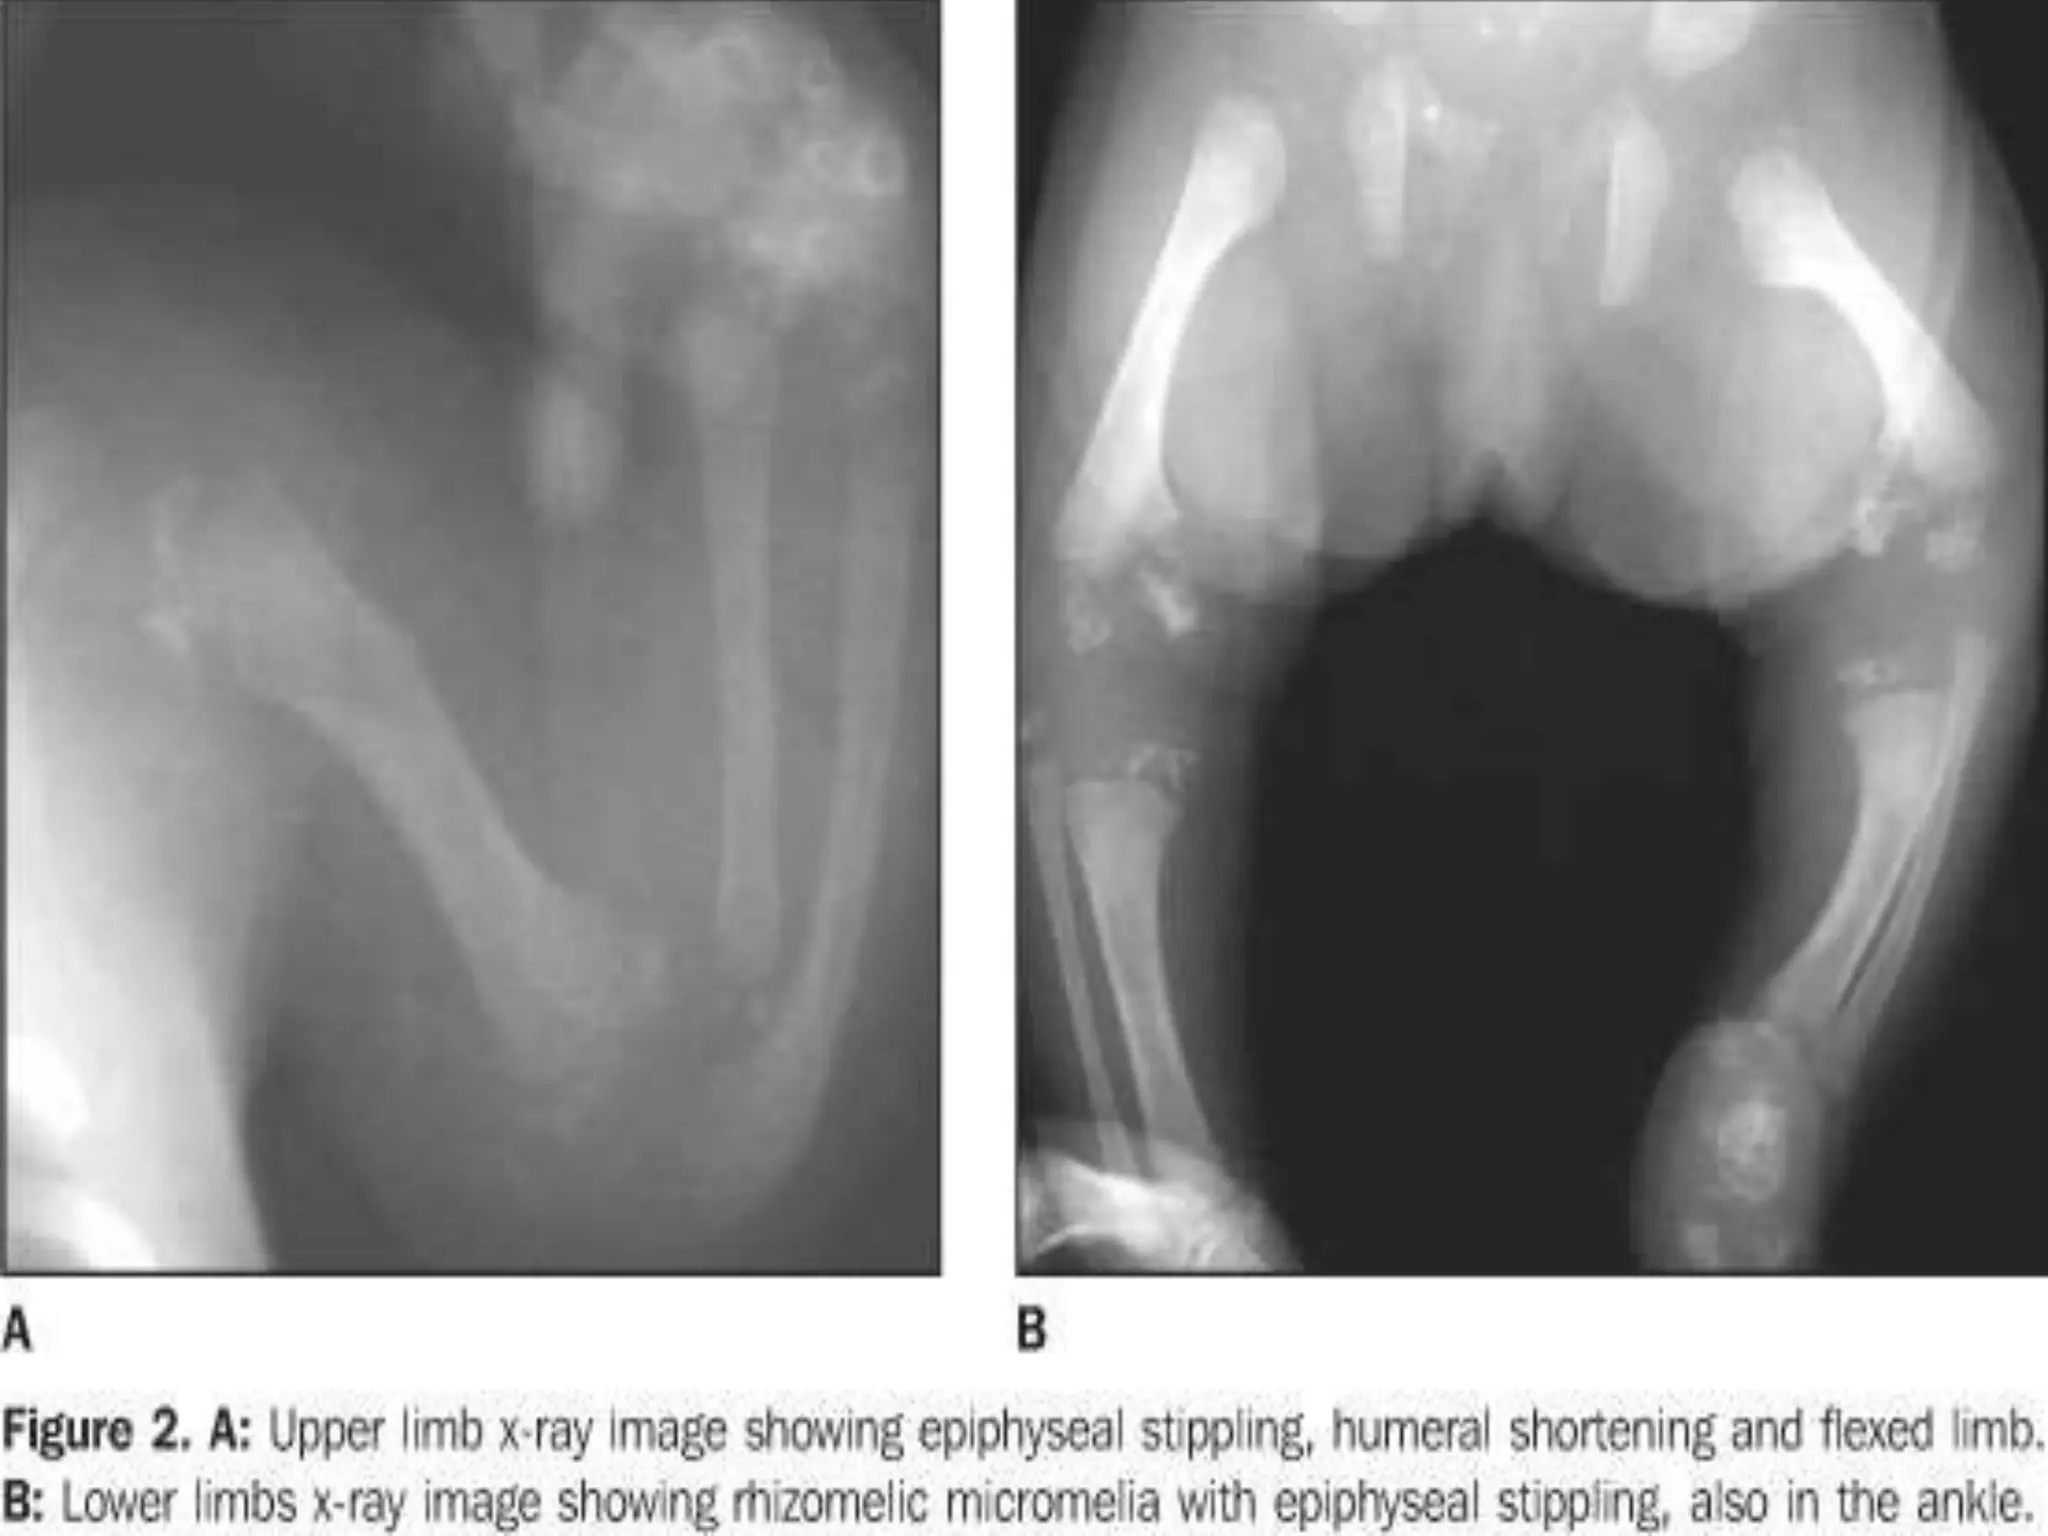

CHONDRO DYSPLASIA PUNCTATA

(SLIPPED EPIPHYSES) or (CONRADI’S DISEASE)

• Multisystem disorder

• Facial abnormalities, vertebral anamolies,

• Asymmetrical epiphyseal changes, bone changes

• Severe cases (cardiac abnormalities, cataracts, mental

retardation)

• X-ray: punctate stippling of cartilagenous epiphyses & apophyses

upto 4 years, later disappear and follow epiphyseal irregularities and

dysplasia.

Stippled epiphyses

CHONDRO DYSPLASIA PUNCTATA (SLIPPEDEPIPHYSES) or (CONRADI’S DISEASE) • Multisystem disorder • Facial abnormalities, vertebral anamolies, • Asymmetrical epiphyseal changes, bone changes • Severe cases (cardiac abnormalities, cataracts, mental retardation) • X-ray: punctate stippling of cartilagenous epiphyses & apophyses upto 4 years, later disappear and follow epiphyseal irregularities and dysplasia.